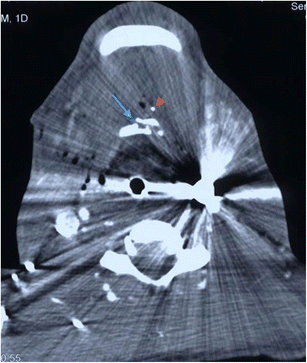

a Axial image of MDCTA performed on a 33-year-old man who sustained a stab injury to left zone 2. The platysma has been breached (arrow) and there is soft tissue emphysema in the deep cervical fascia surrounding the left carotid sheath. No major vascular injury or upper aerodigestive tract penetration was present. There was no pneumothorax. b Axial image of MDCTA through zone 1 on lung-window settings of a different patient who sustained left zone 2 penetrating knife injury with breach of platysma (image not shown). Diffuse soft tissue emphysema is noted in the deep cervical fascia bilaterally in zone 1 despite penetrating wound entry in left zone 2. This can be a common finding in penetrating neck injury where platysma has been breached even in the absence of perforation of the upper aerodigestive tract or pneumothorax. Nevertheless, penetration of the laryngopharynx should be further excluded where clinical and radiological suspicion is high. (Contrast swallow was negative in this patient)